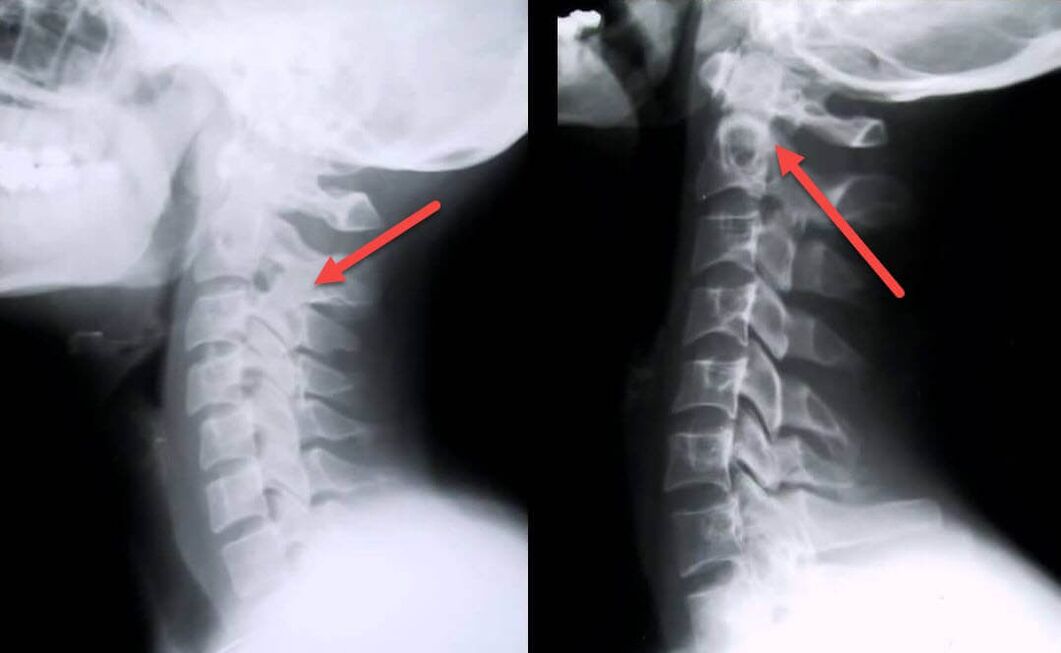

La procédure de diagnostic la plus informative est la radiographie. Les pathologies de 1er degré correspondent au 1er ou au 2ème stade radiologique. Les images obtenues visualisent les signes typiques de la maladie.

| Stades radiologiques de l'ostéochondrose cervicale du 1er degré | Signes caractéristiques |

|---|---|

| Étape 1 | Modifications mineures de la courbure de la colonne vertébrale dans la région cervicale, affectant un ou plusieurs segments |

| Étape 2 | Léger épaississement des disques intervertébraux, déformation des apophyses uncinées, redressement de la lordose, excroissances mineures des structures osseuses |